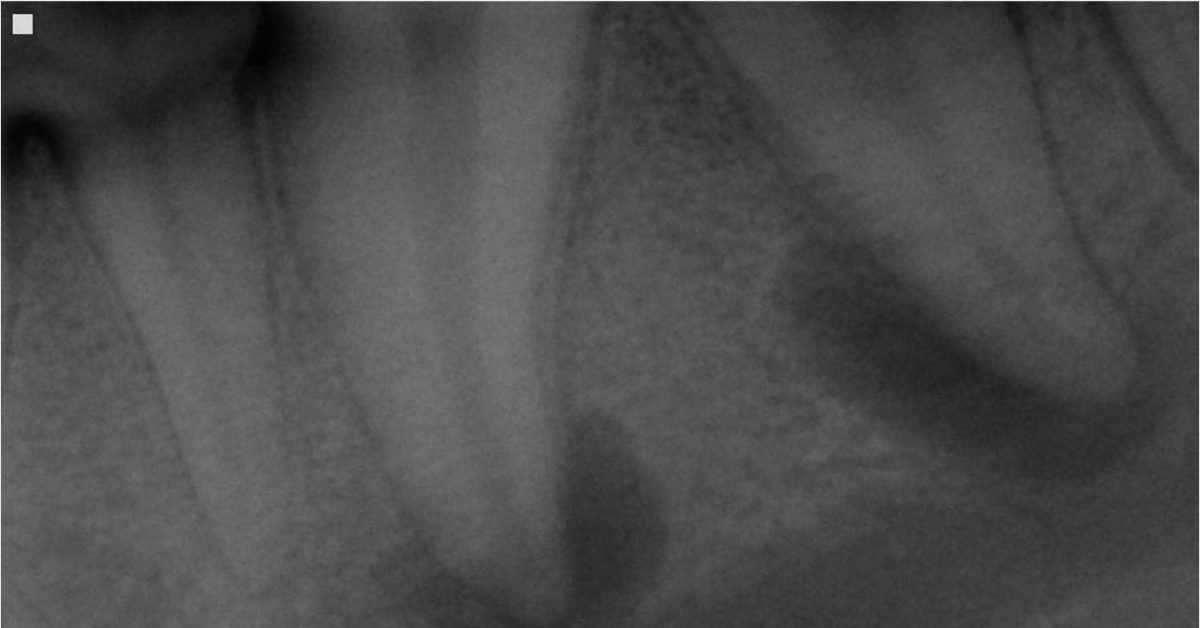

molar abscess radiograph

Treatment for a dog tooth abscess emergency depends on the location, severity, and condition of the affected tooth. Our team begins with a thorough oral examination and diagnostic imaging to understand what is happening below the gumline. This approach allows us to design a plan that focuses on both comfort and long-term stability.